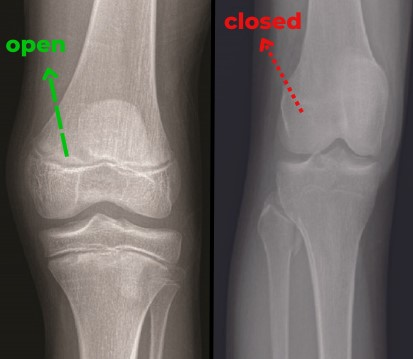

Your bones aren't just calcium sticks holding you upright.